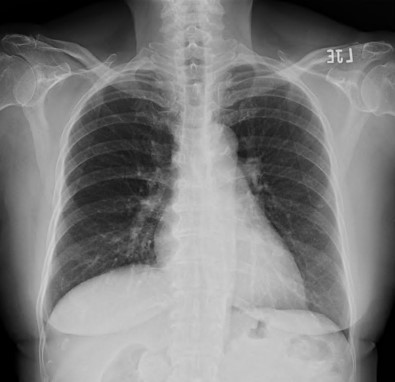

Relevant Test Results Prior to Catheterization

Chest radiography showed no evidence of heart failure. Transthoracic echocardiography demonstrated a left ventricular ejection fraction of 60% with no regional wall-motion abnormalities and no significant valvular heart disease. A myocardial perfusion scan revealed reversible ischemia, suggestive of underlying obstructive coronary artery disease.